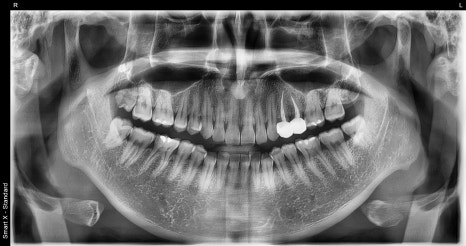

첫 번째 사진: 초진 파노라마 사진입니다. 전체 치아 상태와 발치 및 치료가 필요한 부위를 확인했습니다.